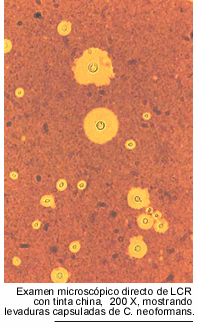

es normal. Por el contrario, el examen microscópico directo, del sedimento

de LCR, con tinta china, acusa la presencia de levaduras capsuladas en el 80

Referente al diagnóstico,

sobresale la importancia del examen microscópico directo del sedimento

del LCR con tinta china, positivo en más del 80 % de los casos y los